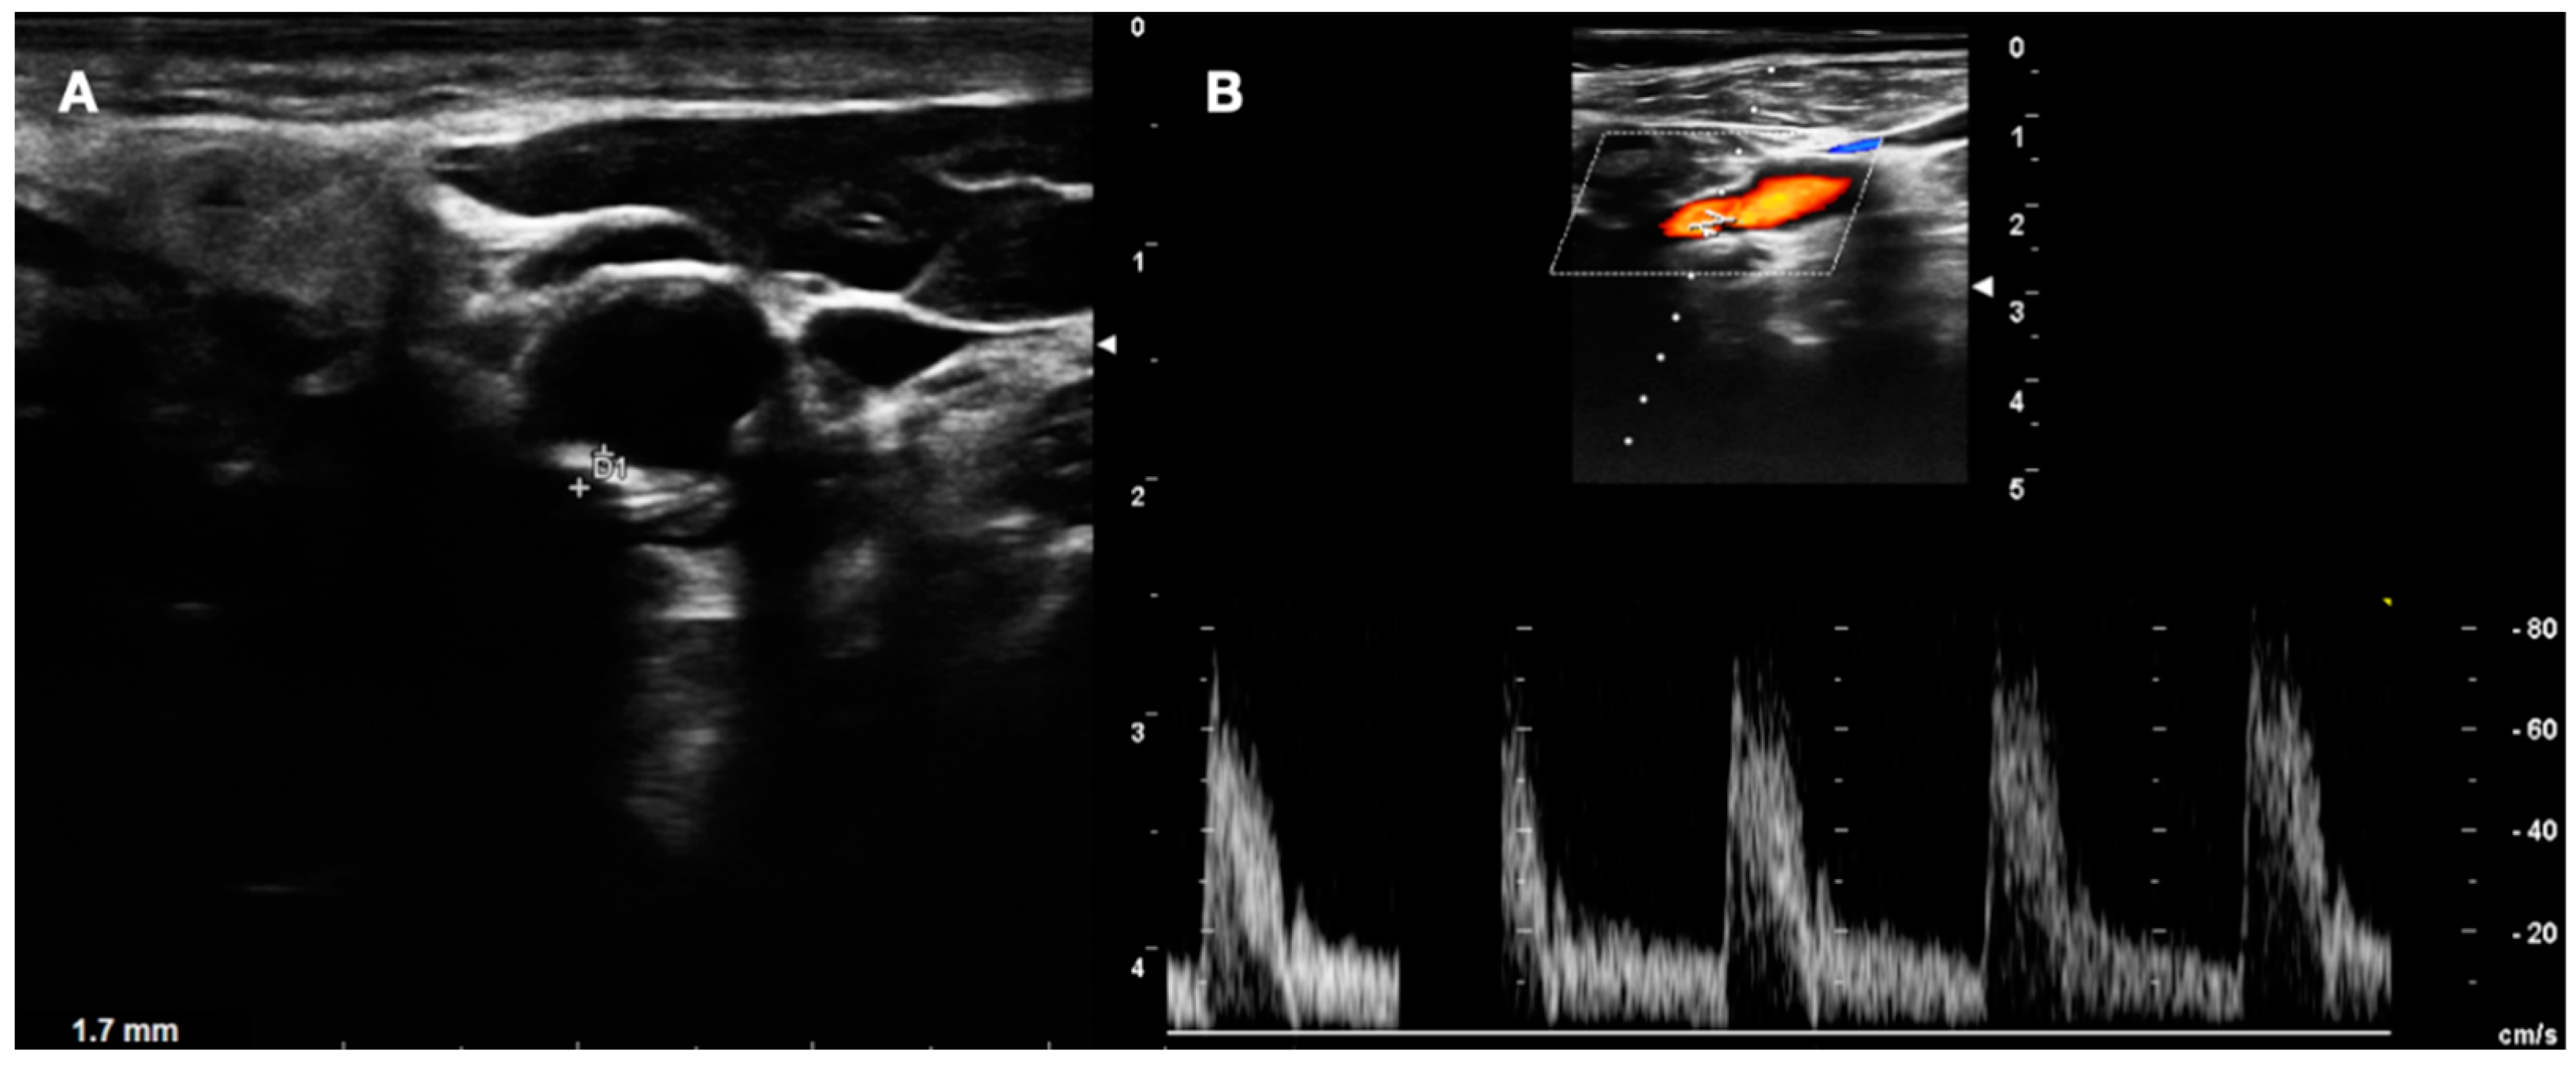

- LOW GRADE and MEDIUM GRADE: Patients presenting a carotid plaque under 30% of stenosis. In these cases, a cardiology evaluation was added, and a clinical path of the main arterial districts (aorta and peripheral arteries) was concluded by DUS (Figure 5 and Figure 6).

Figure 5. DUS images showing plaque in CCA—LOW GRADE (A), and its relative flow (B).

Figure 6. DUS images showing plaque in CCA—MEDIUM GRADE (A), and its relative flow (B).